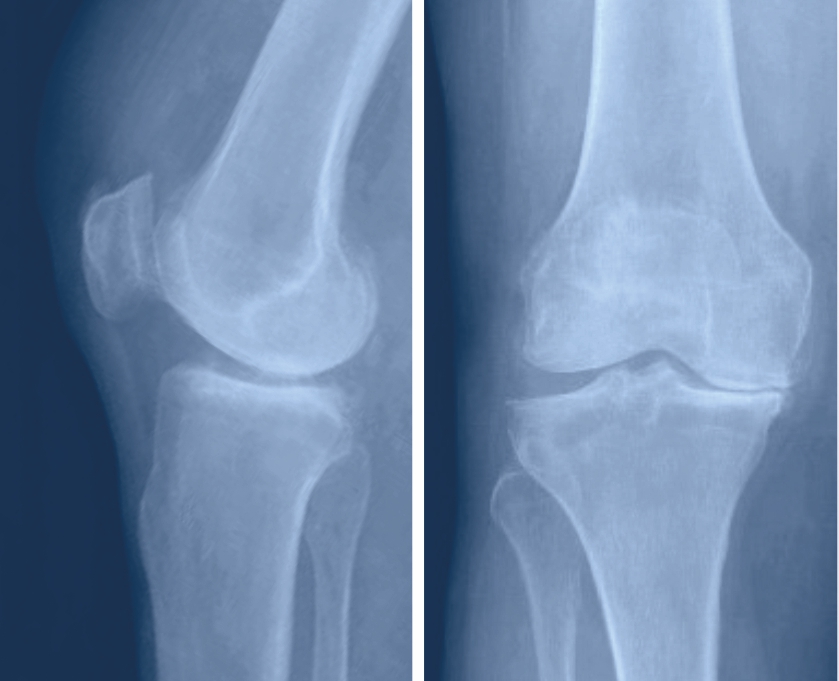

Dieser wird zwischen die Metallteile gesetzt, um die ideale Führung des Gelenks zu gewährleisten und zu verhindern, dass die Metalloberflächen sich aneinander reiben. Je nach Ausweitung der Arthrose besteht heute die Möglichkeit, nicht immer das ganze Knie zu ersetzten sondern gezielt Teilprothesen zu verwenden. Dies hat den Vorteil, dass nur der beschädigte Gelenkanteil ersetzt werden muss.

Die beschädigten Oberflächen des Gelenks werden unter Zuhilfenahme von Schnittschablonen abgetragen, damit das Ersatzgelenk passgenau eingebracht werden kann. Zur genauen Platzierung der Schnittschablonen werden konventionelle Metallinstrumente verwendet, es können aber auch personifizierte Instrumente oder eine Computernavigation zum Einsatz kommen. Durch die Schnittsetzung und die Implantation der Prothese werden grosse Abweichungen der Beinachsen korrigiert, leichte O- oder X-Beine, die der Patient allenfalls schon immer hatte, werden aber belassen.